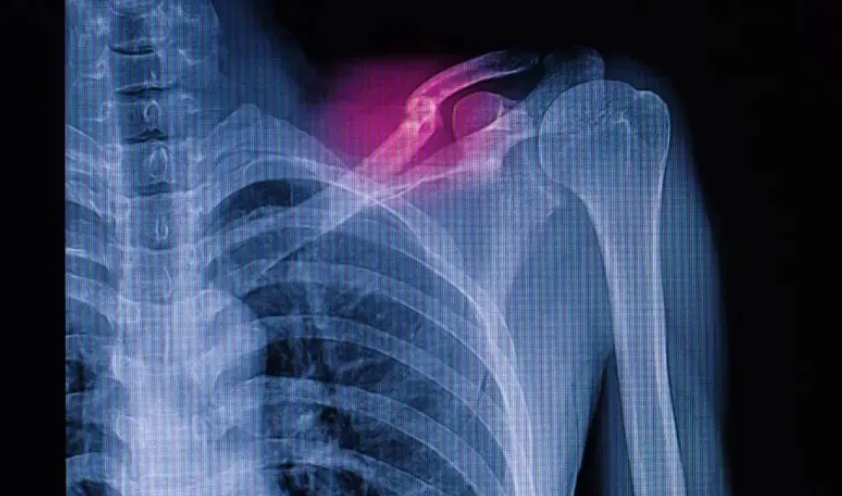

El profesor Kelvin Yeung, líder del proyecto, señaló que las fracturas complejas plantean desafíos médicos significativos debido a las limitaciones de los injertos autólogos y aloinjertos, que conllevan dolor, rechazo e infecciones. Los actuales materiales de fosfato de calcio, aunque biocompatibles, son rígidos y frágiles, lo que no se adapta a los movimientos cotidianos, dificultando la reparación.

La tecnología de nano-clústeres empleada en este cemento permite que sea moldeable antes de su endurecimiento, adecuándose a fracturas irregulares. Al absorber agua, forma microesferas elásticas que rellenan los defectos óseos, facilitando la cirugía y promoviendo la regeneración ósea natural. Según el profesor Wong Tak-man, este avance reduce el tiempo quirúrgico y tiene potencial en neurocirugía y odontología gracias a su estructura porosa que favorece la adhesión celular.